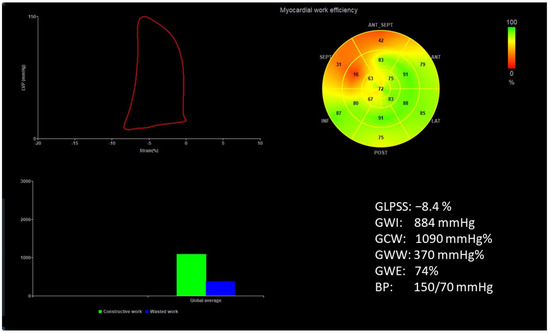

Figure 1 and Figure 2 show two contrasting examples (a healthy person and a patient after myocardial infarction and left bundle branch block) of STE curves with GLPSS, LVEF and LV pressure–strain loops and results of GWE for all LV segments.

Figure 1.

An example of echocardiography of a 30-year-old healthy male. A set of individual longitudinal strain curves for all segments shown in different colors, with the average curve shown as a white dotted line, a bull’s eye of segmental longitudinal peak systolic strains and a summary of global longitudinal peak systolic strain (GLPSS) are shown in the top panel. The LV pressure–strain loop with the bull’s eye representation of myocardial work efficiency for each of the segments and a summary of all myocardial work indices are shown in the lower panel. Abbreviations: GLPSS—global longitudinal peak systolic strain, EF—ejection fraction, GWI—global myocardial work index, GCW—global constructive work, GWW—global wasted work, GWE—global work efficiency, BP—blood pressure.